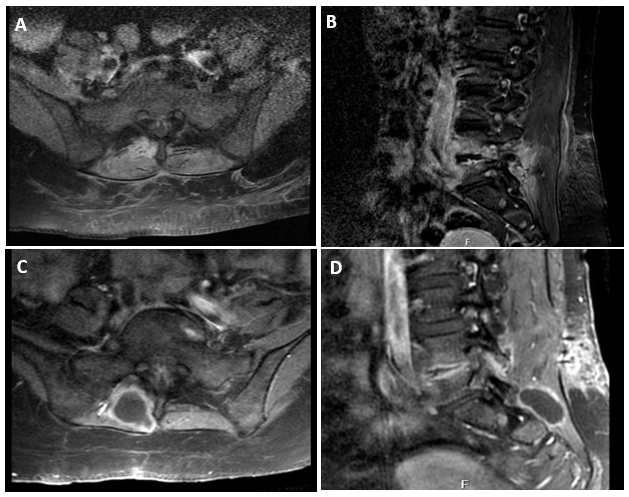

Retained surgical sponge and consequent foreign body reaction is a well-documented complication. In the current literature, the phenomenon has many names such as textiloma, gossypiboma, gauzoma, and muslinoma. While it is one of the widely reported topics, only a few cases are reported by neurosurgeons. Herewith we present a case of textiloma in Turkey who had repeated surgical interventions at various hospitals during the COVID-19 pandemic, possibly due to breakdown of preventive measures against retention of surgical sponge.